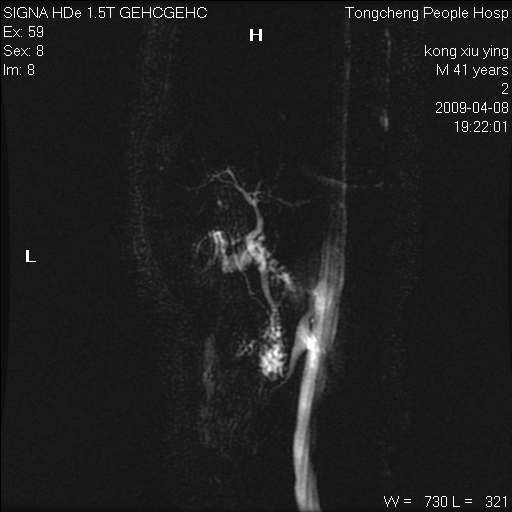

标题: CL1008:【经典】胆囊石榴籽样结石。

女,41岁。健康体检——彩超提示:胆囊显示不清。平素健康,无不适感。

腹部mr扫描及mrcp,图像如下: